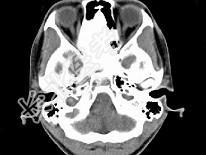

- 单项选择题女,17岁, 鼻阻塞、头痛两年.如图所示符合筛骨病变最可能的诊断是 ( )

B、纤维异常增殖症

E、骨化性纤维瘤